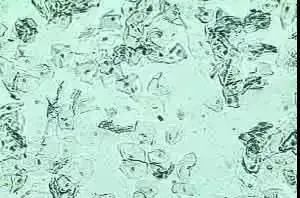

阴道清洁度镜检

阴道清洁度是利用显微镜对阴道分泌物湿片和染色涂片检查,观察其清洁度和有无特殊细菌及细胞等,确认阴道清洁度,判断阴道有无炎症,还可以进一步诊断炎症的原因。

阴道清洁Ⅰ度:镜下以阴道杆菌为主,并可见大量上皮细胞。

阴道清洁Ⅱ度:有部分阴道杆菌及上皮细胞,部分白细胞和杂菌。

阴道清洁Ⅲ度:少量阴道杆菌和上皮细胞,大量白细胞和其他杂菌。提示炎症,如阴道炎、宫颈炎。

阴道清洁Ⅳ度:镜下无阴道杆菌,几乎全是白细胞和大量杂菌。多见于严重阴道炎,如淋球菌阴道炎、滴虫性阴道炎等。

在悬滴液中,正常白带高倍视野仅能看到一、二个白细胞,如存在大量白细胞应考虑滴虫病或宫颈炎;念珠菌病及细菌性阴道病白带的悬滴液涂片中白细胞少。